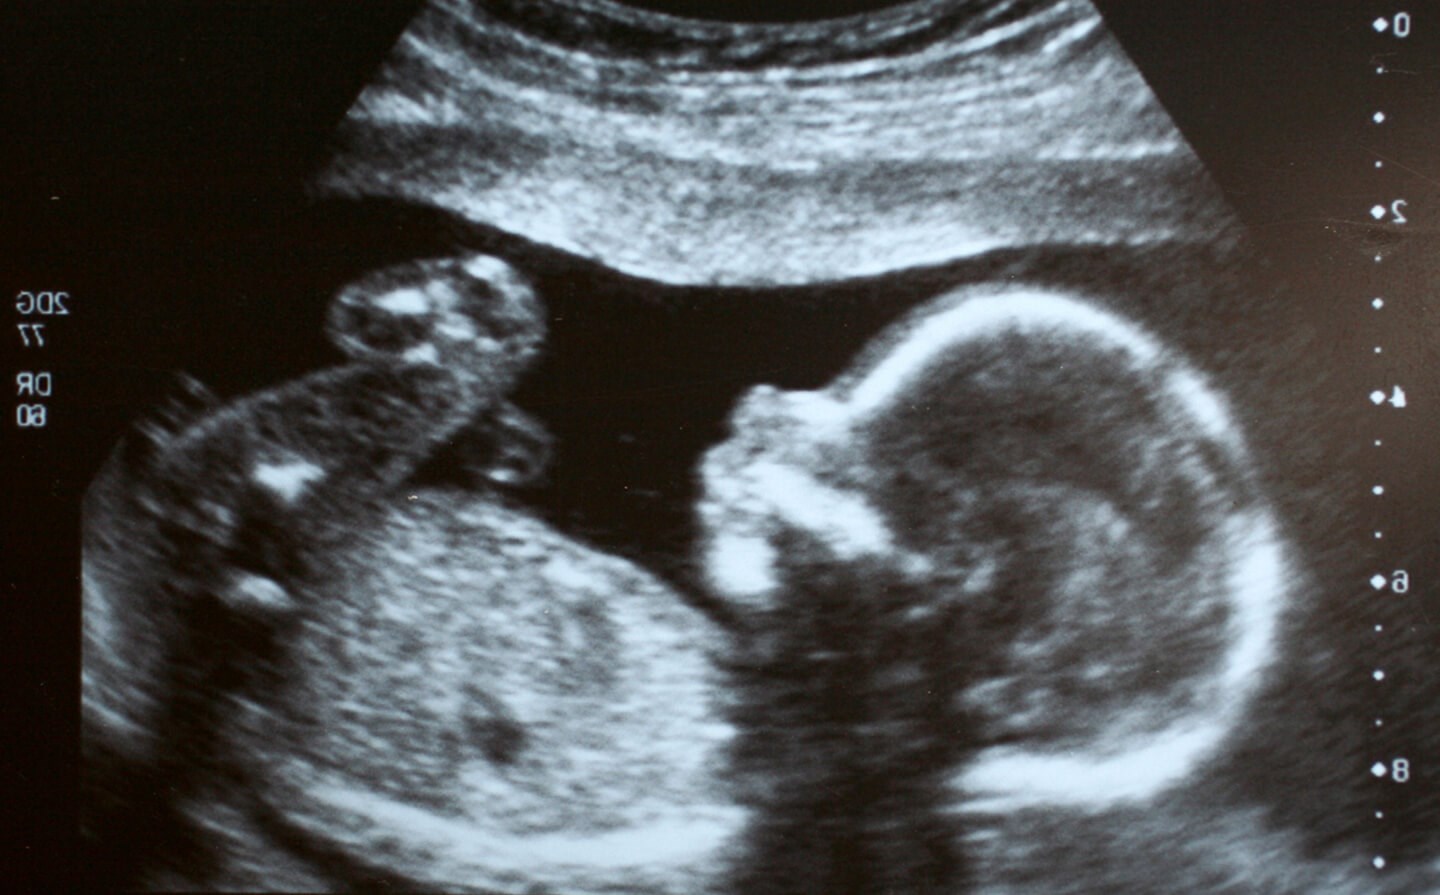

Gravidez: 20ª semana | 5º mês | 2º trimestre

Esta é considerada a ecografia mais importante da gravidez, a ecografia morfológica. Este exame, realizado entre as 18 e as 24 semanas, tem como principais objetivos avaliar pormenorizadamente a anatomia fetal, verificar o ritmo de crescimento do bebé, determinar a localização placentar e quantificar o líquido amniótico. A avaliação rigorosa da anatomia fetal permite detetar a maior parte das malformações congénitas, mas não todas. Existem algumas doenças, felizmente raras, cujo diagnóstico pré-natal não é possível pela ecografia. Neste exame é também efetuada a medição do comprimento do seu colo do útero que permite definir o risco do bebé nascer antes das 37 semanas. E, claro, saber com toda a certeza se é menino ou menina.